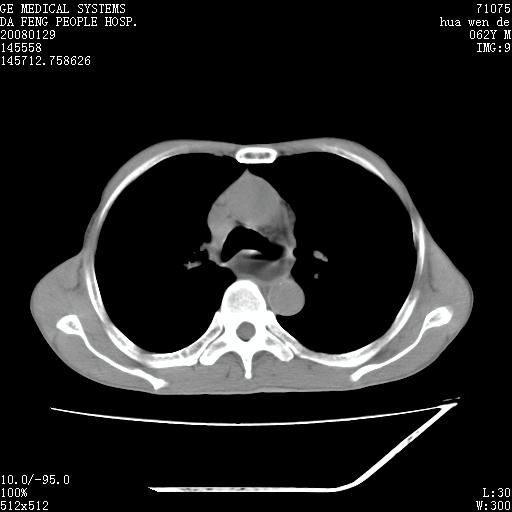

男性,67岁。作肺部检查时发现

理由:1、右上肺内病灶,空洞形成,有液平。

2、肺内多处炎症。

1.整个食管扩张,未见明显占位性病变,贲门区亦未见明显占位病变,考虑:贲门失驰缓症;

2.右上肺病变边缘可见毛刺,囊壁厚度不均匀,周围境界较清楚,未见炎性渗出性影,右上肺外带可见片状影,边缘不清,考虑:肺癌伴空洞形成、右上肺炎。

食管全程扩张,壁均匀不厚,喷门失弛缓症

右上肺空洞可见液平,临近肺野磨玻璃密度,考虑1.结核2.脓肿

右上肺空洞可见液平,临近肺野磨玻璃密度,考虑1.结核2.脓肿 支持!